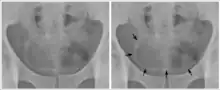

- Cystite et urétérite (S. haematobium) avec hématurie, qui peut évoluer en cancer de la vessie (carcinome épidermoïde) ;